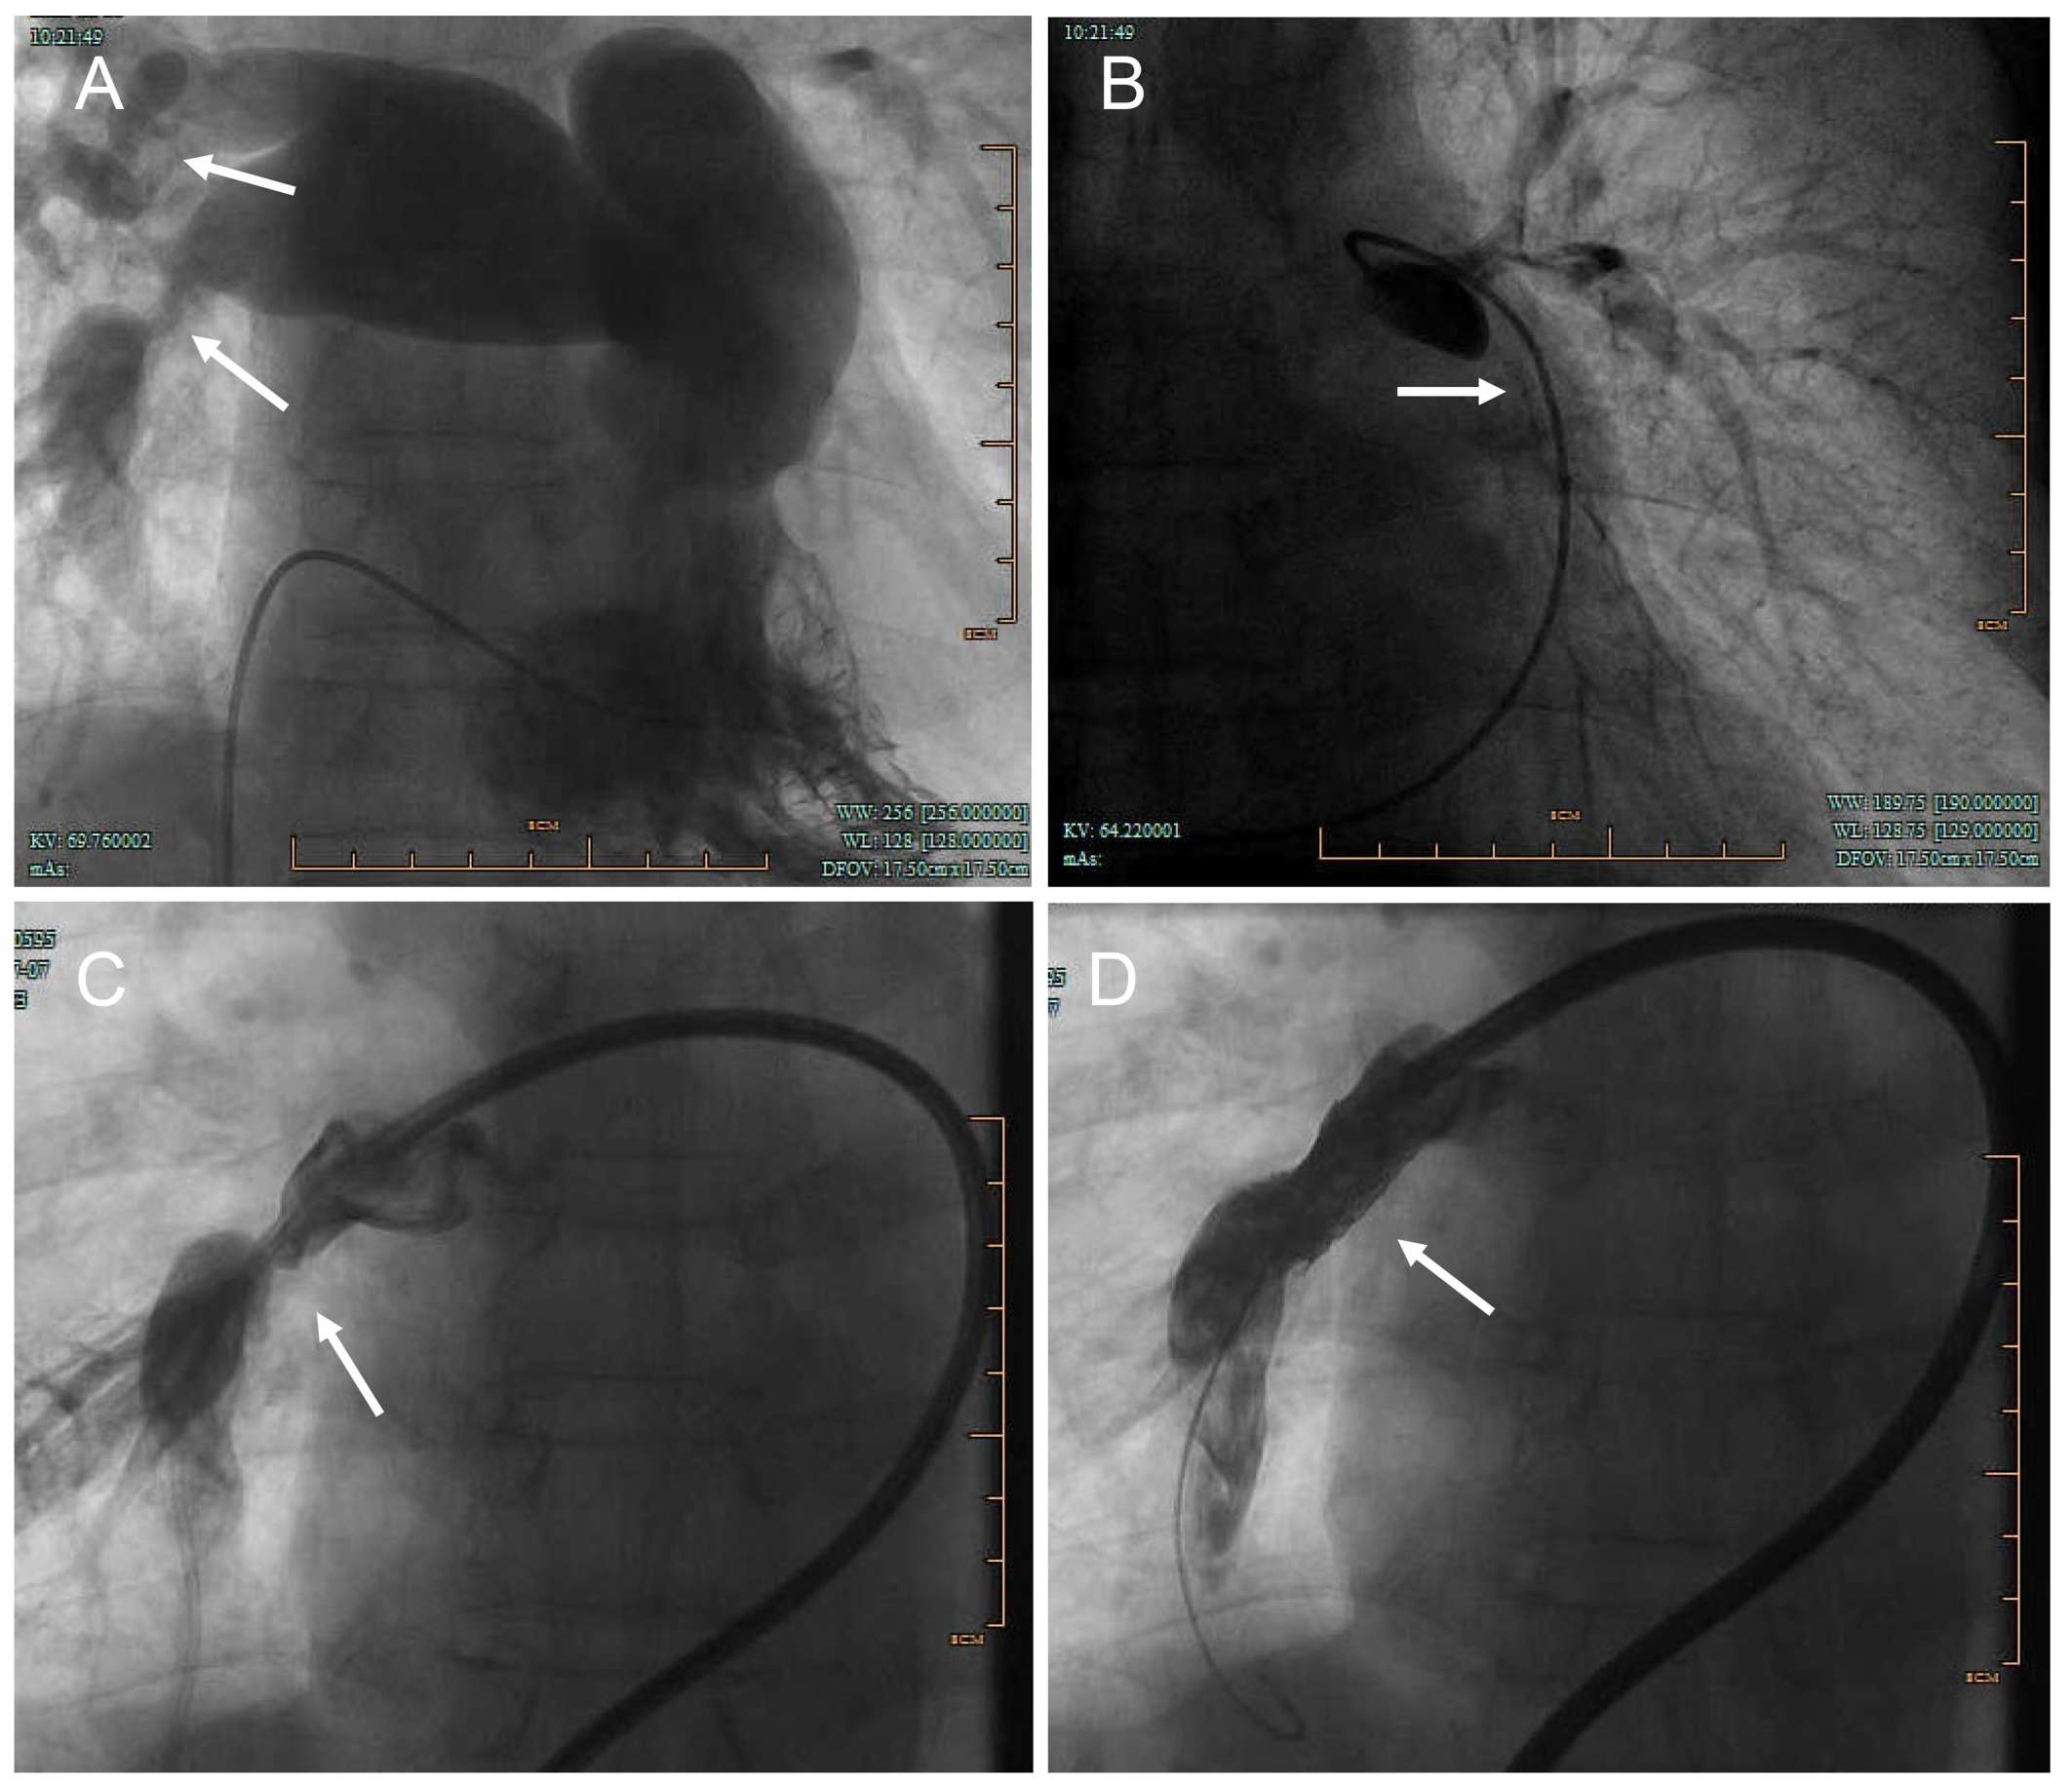

Abstract Body (Do not enter title and authors here): Introduction:Fibrosing mediastinitis is a rare condition characterized by excessive fibrous tissue proliferation in the mediastinum, leading to compression of vital structures. We present a case of idiopathic fibrosing mediastinitis with progressive pulmonary hypertension and multi-vessel stenosis, highlighting diagnostic challenges and management strategies. Research Questions: The case explores the clinical and imaging features of fibrosing mediastinitis, its differentiation from other causes of pulmonary hypertension, and the potential treatment options for fibrosing mediastinitis-related vascular obstruction. Aims: This case aims to (1) describe the clinical course and diagnostic pitfalls in a patient with long-standing fibrosing mediastinitis, (2) evaluate the role of imaging and invasive testing in diagnosis, and (3) assess the efficacy of endovascular stenting in symptomatic relief. Methods: A 58-year-old male with a 5-year history of recurrent dyspnea and chest tightness underwent serial evaluations, including CT angiography, echocardiography, pulmonary function tests, bronchoscopy, and right heart catheterization. After failing medical therapy, he underwent percutaneous pulmonary artery stenting. Results: Imaging revealed mediastinal lymphadenopathy with calcification, pulmonary artery stenosis, and tracheobronchial compression. Pulmonary arteriography confirmed severe stenosis in multiple pulmonary arteries. Stent implantation improved exercise capacity (6-minute walk distance: 360m to 485m) and oxygen saturation. Conclusions: Fibrosing mediastinitis is a rare but treatable cause of pulmonary hypertension. A high index of suspicion is needed in patients with progressive dyspnea and mediastinal fibrosis. Endovascular stenting may provide symptomatic relief in select cases, though long-term outcomes require further study.